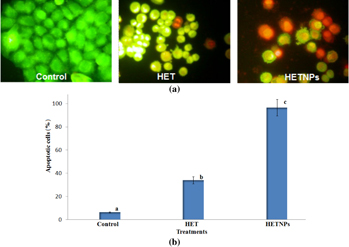

DNA-binding dyes AO and EB were used for the morphological apoptotic and necrotic cells [30]. AO is taken up by both viable and non-viable cells and emits green fluorescence if intercalated into double stranded nucleic acid (DNA). EB is taken up only by non-viable cells and emits orange red fluorescence by intercalation into DNA. After treatment with IC50 dose of HET and HETNPs for 48 h, the cells were detached, washed by cold PBS and then stained with a mixture of AO (100 μg ml−1) and EB (100 μg ml−1) at room temperature for 5 min. The stained cells were observed by a fluorescence microscope at 40 × magnifications.

Morphological features of apoptosis such as chromatin condensation, nuclear fragmentation, alterations in the size and the shape of cells, as revealed by fluorescence microscopic analysis. Staining with acridine orange (AO) and ethidium bromide (EB) showed significant fragmentation and condensation of chromatin in KB cells treated with native HET and HETNPs for 48 h (figure 10(a)). While the control cells exhibited a normal nuclear morphology characterized by a diffused chromatin structure and, therefore, light green staining (figures 10(a) and (b)) shows the quantitative result of apoptosis in the control, native HET and HETNPs treatment.

Figure 10. (a) Fluorescence microscopic images of apoptotic morphology by dual staining and (b) percentage of apoptosis.

Apoptosis is a gene-regulated phenomenon induced by many chemotherapeutic agents in cancer treatment and the characters of apoptosis including chromatin condensation, cell and nuclear shrinkage, membrane blebbing and oligonucleosomal DNA fragmentation [45, 46]. Among various methods used to detect apoptosis, chromatin condensation and nuclear fragmentation remain the hallmarks of apoptotic cells, since it allows distinguishing viable, early or late apoptotic and necrotic cells. In AO/EB double staining, AO permeates all cells and makes the nuclei appear green, whereas EB stains the nucleus red only when cytoplasmic membrane integrity is lost. Thus, live cells show a normal green nucleus, early apoptotic cells show a bright green nucleus with condensed or fragmented chromatin, late apoptotic cells show condensed and fragmented orange chromatin and cells that have died from direct necrosis show a structurally normal orange nucleus [30, 47]. In the present study, AO/EB staining also exhibited a higher number of apoptotic cells on treatment with HETNPs compared with native HET and control (figure 10(a)). The increased ROS levels and changes in the MMP might be the reason for the increased apoptotic morphological changes. It might also be due to the better uptake of nanoparticulate HET which resulted in greater accumulation of delivered HET inside cancer cells accompany by its sustained release, exerting a higher percentage of cells in apoptotic phase.